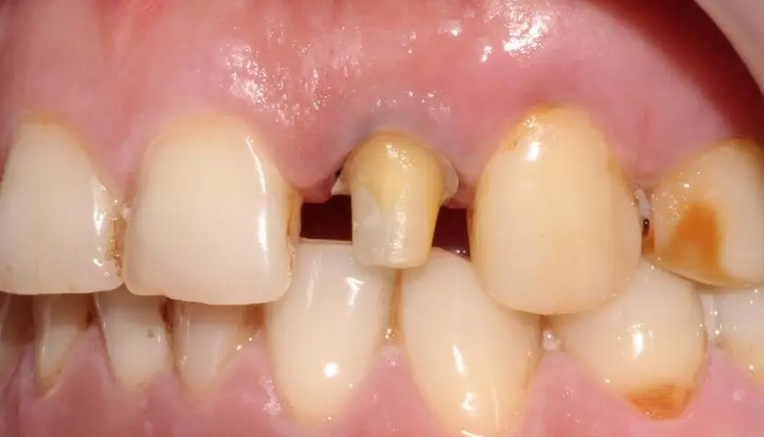

根管不做冠,早晚是后患!患者“不做冠”后牙齿劈成了两半!